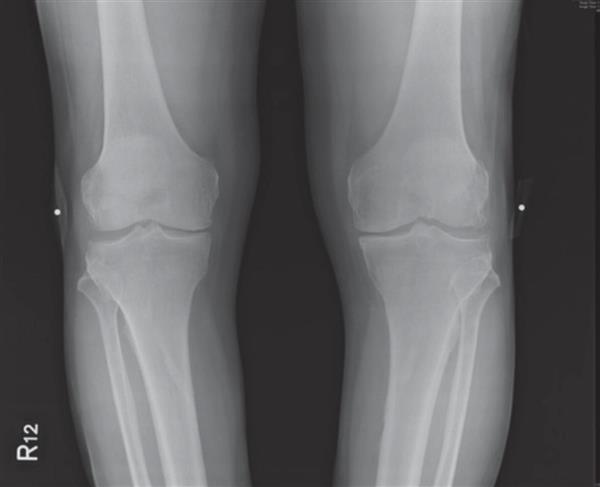

吳先生,七十五歲,居住於新竹縣,診斷:右膝為較嚴重的第三期退化性關節炎,左膝為第四期退化性關節炎。

去年,接受治療前的X光片,兩膝內側關節間隙幾乎消失,右膝第三期,左膝已是第四期。

▲手術前

▲手術後一年

ACRFP術後滿一年的X光片,關節間隙變寬,有明顯改善。我們對這結果都非常滿意。一年來,吳先生未曾服藥,如果能繼續做適當的保健,原本需要置換人工關節的膝關節,應可逐年改善。又是一個「軟骨能自然修復」的見證!